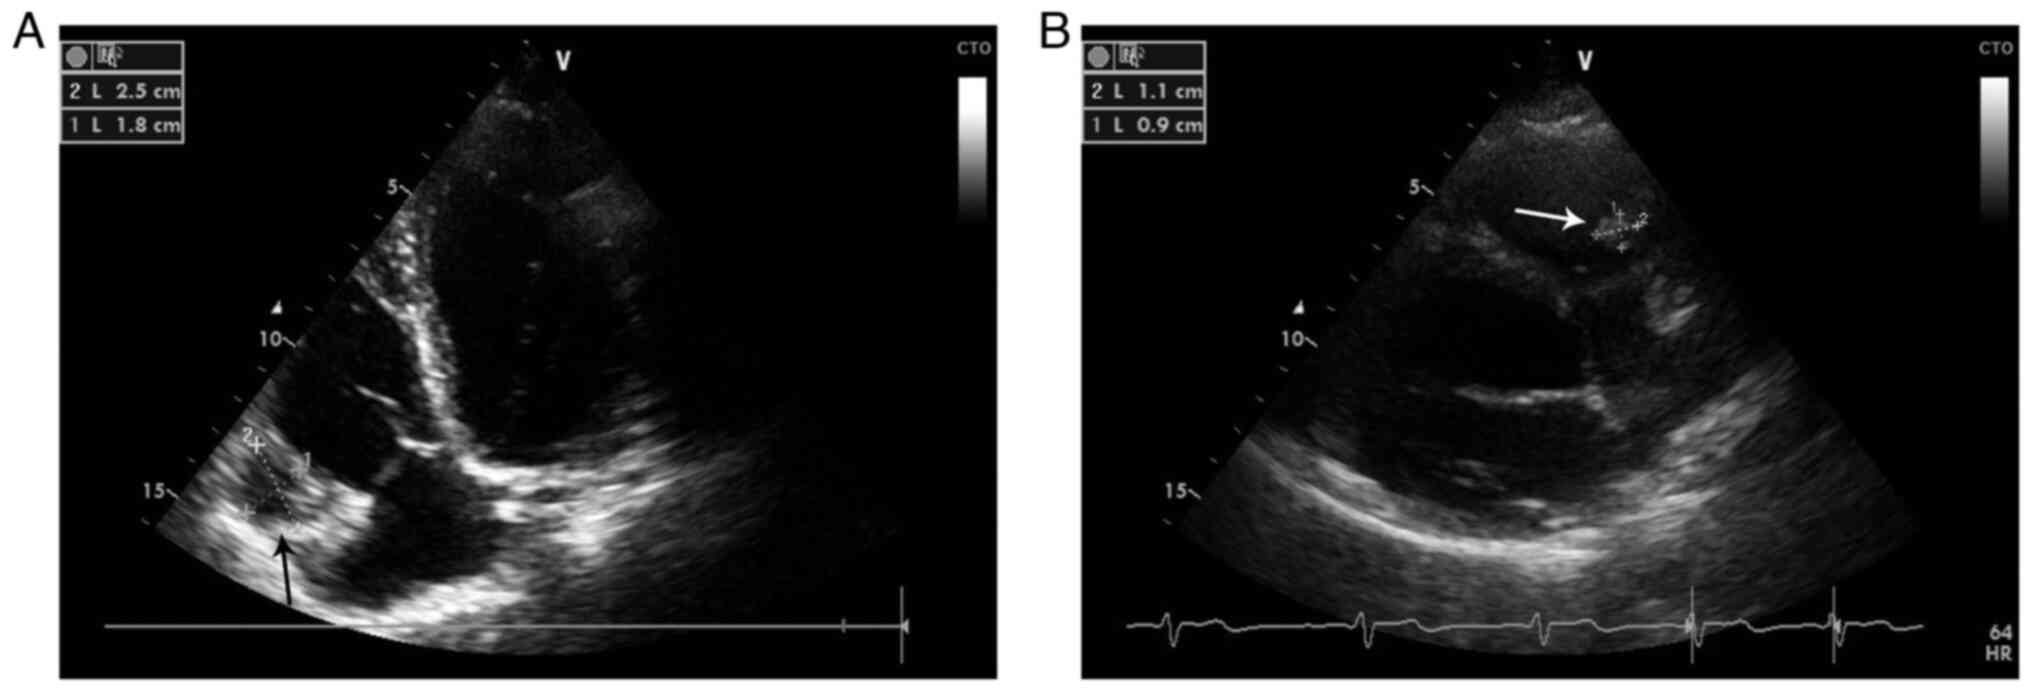

Following admission to the Department of Cardiology, the patient had no fever, was hemodynamically stable, had a normal respiratory rate, had 94% oxygen saturation while breathing ambient air and exhibited barely audible respiratory sounds in his left lung basal segment, as well as fine rales. Routine laboratory tests demonstrated eosinophilia (12.2%; normal cut off, 5%), elevated D-dimer (464 ng/ml; normal cut off, 250 ng/ml) and elevated C-reactive protein (3.9 mg/dl; normal cut off, 0.3 mg/dl) levels. A standard electrocardiogram demonstrated an S1Q3T3 pattern and nonspecific intraventricular conduction delay in the inferior leads (Fig. 2). Furthermore, transthoracic echocardiography (TTE) revealed a slightly enlarged right ventricle (RV), with moderate RV systolic dysfunction, as well as a bi-lobular mass attached to the right ventricular free wall adjacent to the right ventricular inflow, without causing any inflow obstruction (Fig. 3A). Transesophageal echocardiography did not provide any additional information. Furthermore, at that time, the patient had no other organ involvement. During hospitalization, the patient received low molecular weight heparin (enoxaparin, 60 mg/0.6 ml twice-daily by subcutaneous injection) and a parasitology exam was requested. The ELISA assay (SERION ELISA Classic; SERION Diagnostics) was positive for E. granulosus IgG antibodies (10.18 U/ml; normal cut off, 1.1 U/ml) and therefore antiparasitic treatment using albendazole (400 mg, twice daily) was administered. During hospitalization, the clinical evolution improved and the patient became stable and asymptomatic. The patient was discharged with conservative treatment (albendazole, 400 mg twice-daily; levocetirizine, 5 mg twice-daily) and a recommendation for cardiac surgery evaluation, which the patient refused. In the first year of clinical evolution, the patient was assessed in the Department of Cardiology twice and was stable and asymptomatic. Serial transthoracic echocardiograms demonstrated a marked reduction in the dimensions of the RV cardiac cyst and an increase in its echogenicity (Fig. 3B).

Figure 3

Transthoracic echocardiography presenting (A) initial presentation a slightly enlarged RV, moderate RV systolic dysfunction and a bi-lobular mass attached to the free right ventricular wall adjacent to the tricuspid valve causing no obstruction (arrow), and a (B) marked reduction in dimensions of the RV cardiac cyst and an increase of its echogenicity (1-year follow-up). RV, right ventricle.